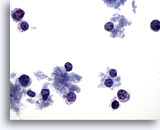

Figure 47

Breast FNA, Lobular carcinoma.

Lobular carcinoma aspirates tend to be sparsely cellular, but occasionally contain many cells as in this example. The tumor cells are single, but may form small aggregates, often with a single file appearance. 20x

Figure 47

Breast FNA, Lobular carcinoma.

Lobular carcinoma aspirates tend to be sparsely cellular, but occasionally contain many cells as in this example. The tumor cells are single, but may form small aggregates, often with a single file appearance.

20x